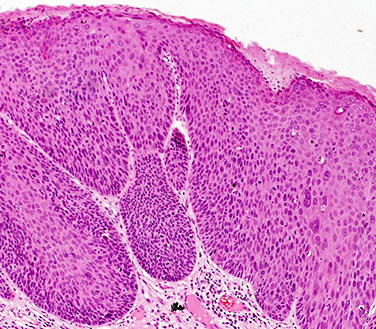

Squamous cell hyperplasia

aka hyperplastic dystrophy or lichen simplex chronicus

- non-specific rxn to pruritis

- may be present at the borders of malignant lesions

Micro: can have inc mits, but lacks atypia